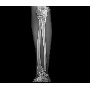

Klinikai esetek 2.